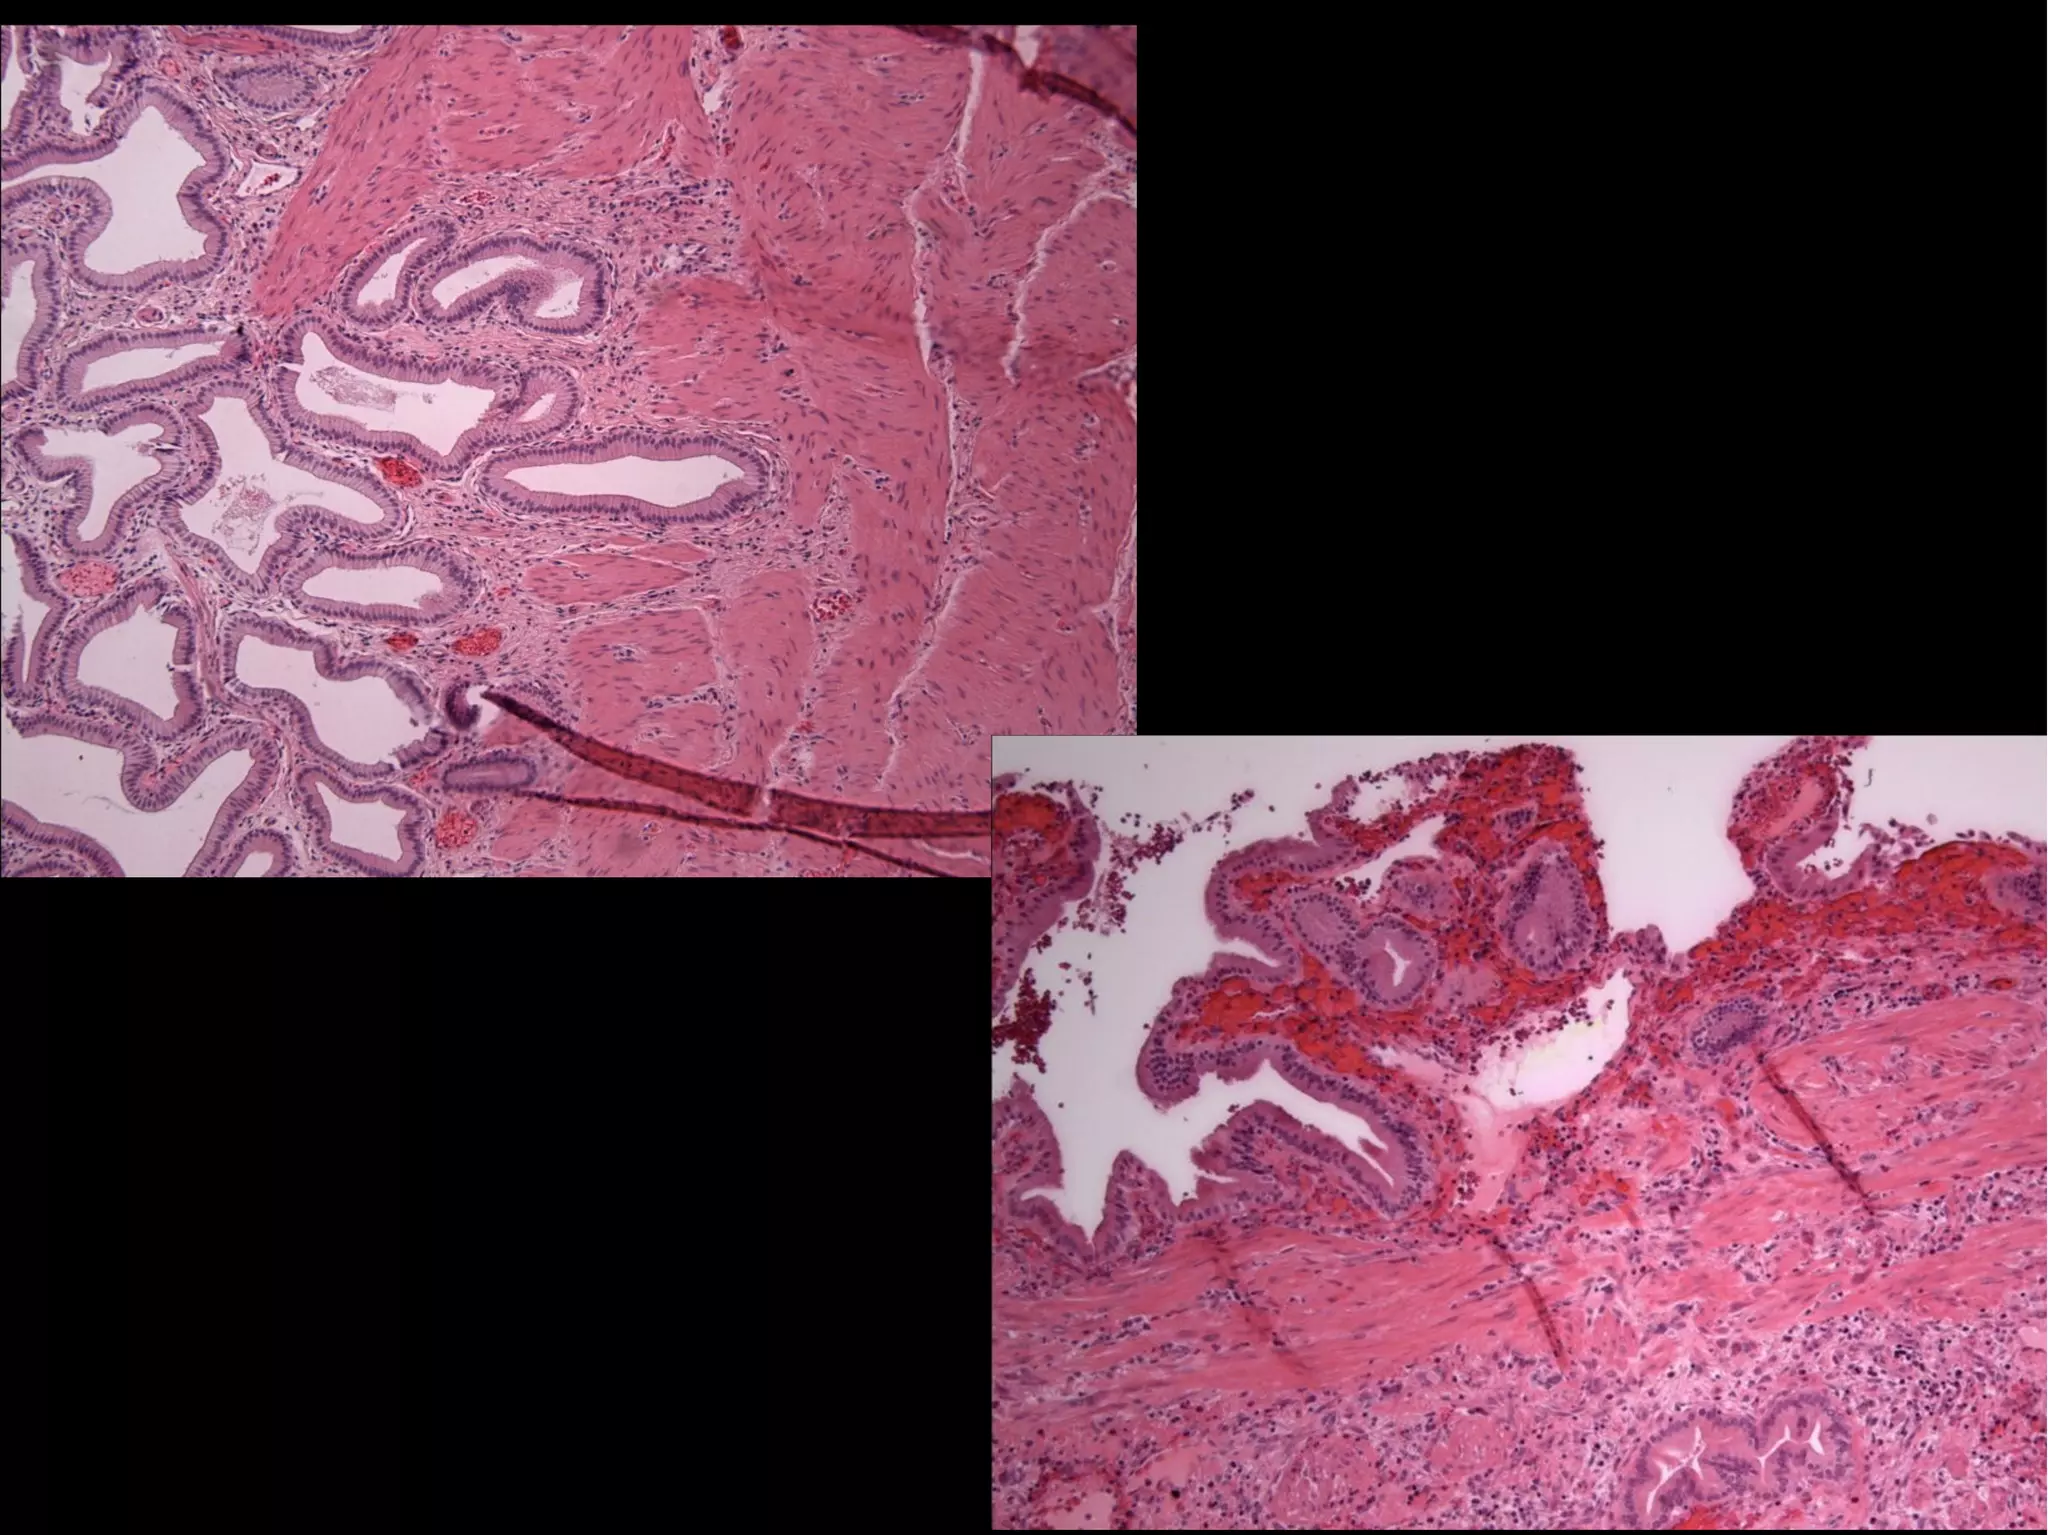

• #5 Los cambios histológicos que con mayor frecuencia se pueden observan en estos casos son fibrosis leve de la pared vesicular con mucosa sin alteraciones y en algunos pacientes con múltiples episodios recidivantes de cólico biliar puede haber una vesícula escleroatrófica y divertículos intramurales conocidos como senos de Rokitansky-Aschoff. Cuando persiste el cálculo impactado en el conducto cístico, además del factor mecánico, se desarrollan cambios bioquímicos y anatómicos en la mucosa secundarios a la estasis biliar, estos cambios parecen ser indispensables para desencadenar la respuesta inflamatoria, misma que se suma al edema de la pared que favorece obstrucción venosa y linfática, isquemia y necrosis. Los cambios histológicos de colecistitis crónica pueden ser secundarios a la irritación mecánica persistente de la litiasis o a episodios obstructivos o inflamatorios agudos previos, sin que el daño se relacione con los síntomas o con mayor morbilidad. (1,4,10)

• #6 Aspecto macroscópico de vesícula biliar después de seccionarla longitudinalmente. Notar el engrosamiento de la pared, abundantes cálculos polihédricos y un pequeño tumor papilar en el conducto cístico. Proliferacion papilar de la mucosa biliar Nervio periferico infiltrado por adenoca vesicula biliar Caracteristicas histologicas del adenocarcinoma